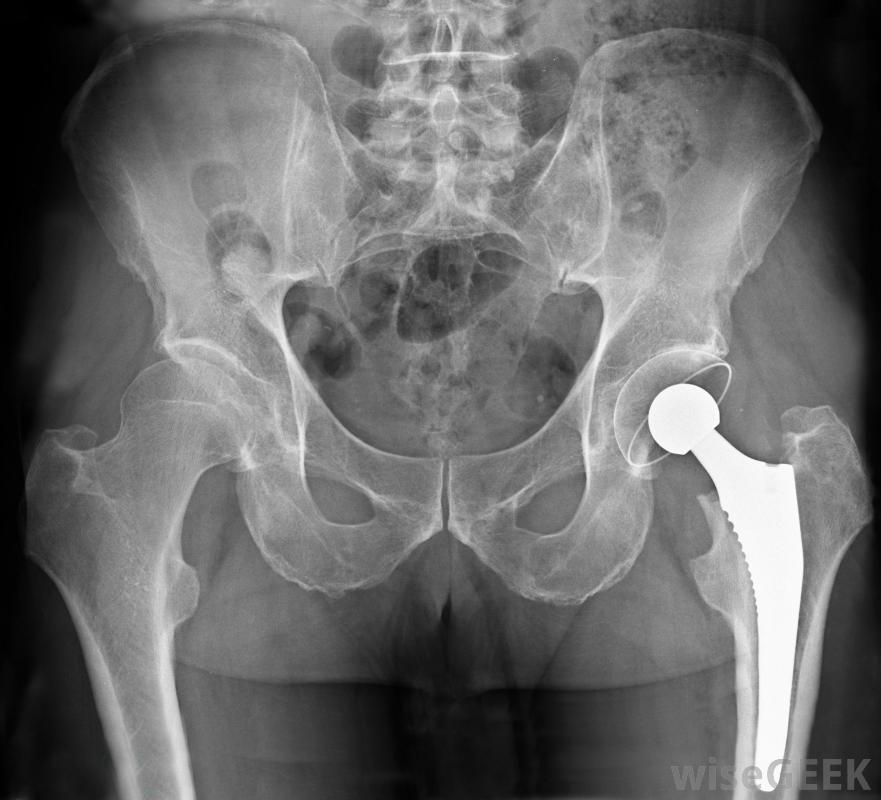

髋关节置换手术有时是选择性手术。